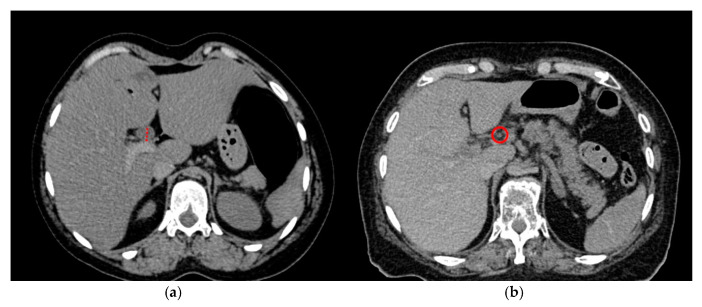

All our cases had undergone postmortem computed tomography (PMCT) before autopsy. PMCT was performed with a 128-slice scanner (SOMATOM Definition Flash, Siemens Healthineers, Erlangen, Germany) with bodies in the supine position using automatic dose modulation (CARE Dose 4D™, Siemens Healthineers, Erlangen, Germany). The imaging parameters included tube voltage, 120 kVp, and slice collimation, 128 × 0.6 mm. PMCT data were reviewed on a Syngo system imaging software VB40 for multimodality reading (Syngo. via, Siemens Healthineers, Erlangen, Germany). A medical student under the supervision of both a board-certified radiologist and a forensic pathologist performed a blinded read-out for these PMCT data (soft kernel reconstruction B30s, soft tissue window), namely, a measurement of the CBD diameter and an evaluation of the gallbladder (present versus post-cholecystectomy) and summarizing the data in an excel sheet (Figure 1). Additionally, the dataset was assessed for the presence of decomposition gas. Cases in which decomposition gas were found in the vascular system or organs were excluded.